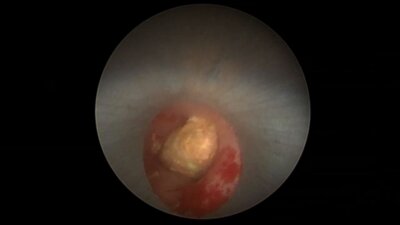

II – Урологическая школа тулиевых технологий